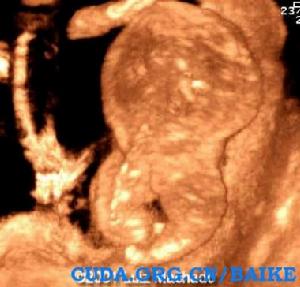

超聲特徵:

· 特徵性表現是都卜勒出現反向動脈灌注。可見臍動脈血流從胎盤朝向無心胎,靜脈血流則反向。這是由於無心胎沒有心臟泵血只能依靠與胎盤的動脈-動脈交通從正常胎兒處竊血。

· 異常胎兒頭極,心臟,上肢及許多內臟受損。下肢相對保持但是足內翻和腳趾異常普遍可見。

超聲圖例: